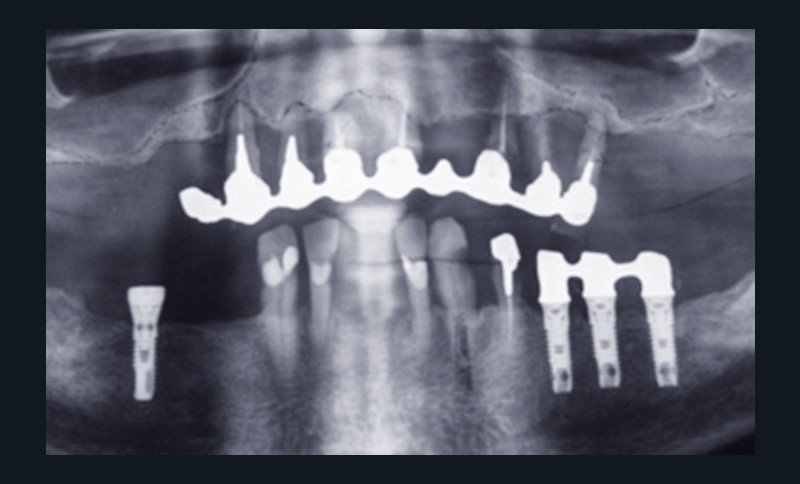

2) Devant l’urgence du problème, le traitement est initié au maxillaire. Le patient, ne désirant pas de chirurgie par comblement sous sinusien, six implants Cortex® (Co Mua) sont mis en place, dont un Saturn en position 21 et cinq Dynamix en situation 12, 14, 16 (angulé à 30°) et en situation 23 et 25 (angulé à 30°).

Des piliers multiunit Cortex® (Co Mua) sont vissés sur les implants, et l’ensemble est mis en charge immédiate par un bridge provisoire en résine acrylique renforcé au composite (fig. 3).